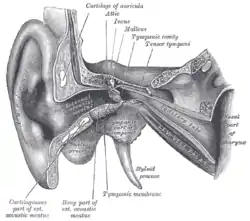

External and middle ear, right side, opened from the front (coronal section)

External and middle ear, right side, opened from the front (coronal section) Horizontal section through left ear; upper half of section

Horizontal section through left ear; upper half of section The right membrana tympani with the hammer and the chorda tympani, viewed from within, from behind, and from above